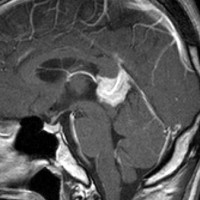

この例は古いので第3脳室開窓術 ETV をしていません。左はICE化学療法前。中央は9日後。右は25日後です。閉塞性水頭症があっても1週間くらいで中脳水道が通って水頭症は改善します。ジャーミノーマであれば,ICE化学療法1コースでかなり縮小するはずです。このような顕著な効果がない時には,逆にジャーミノーマ以外の胚細胞腫瘍が混在していると考えた方がいいでしょう。多くは奇形腫の混在です。